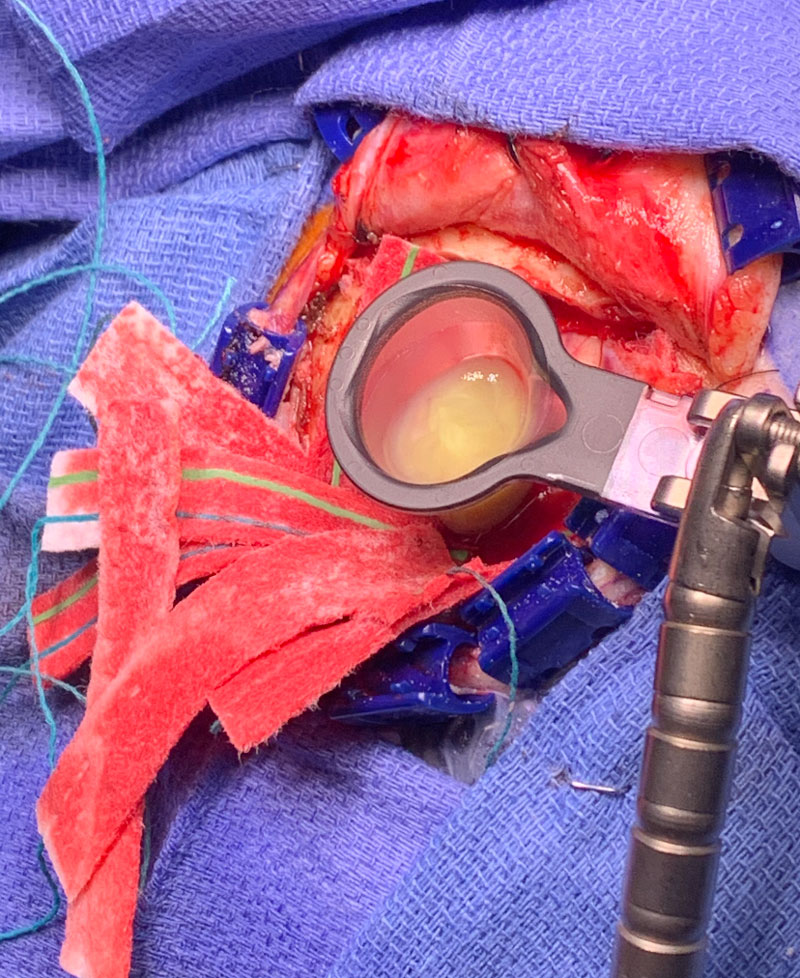

This is a 50 year old man who last year had undergone gastrectomy for gastric cancer. He presented now with new onset of lethargy and aphasia, with both a receptive and expressive component . He was also experiencing intermittent bradycardia. Brain imaging showed a 3 cm ring enhancing , fluid filled mass in the left frontal region with significant surrounding edema, mass effect, and midline shift. (Image 1 shows axial post contrast MRI. ) Recent imaging of the body had shown no evidence of active metastatic disease.

Image 1: Pre-treatment axial post contrast MRI.